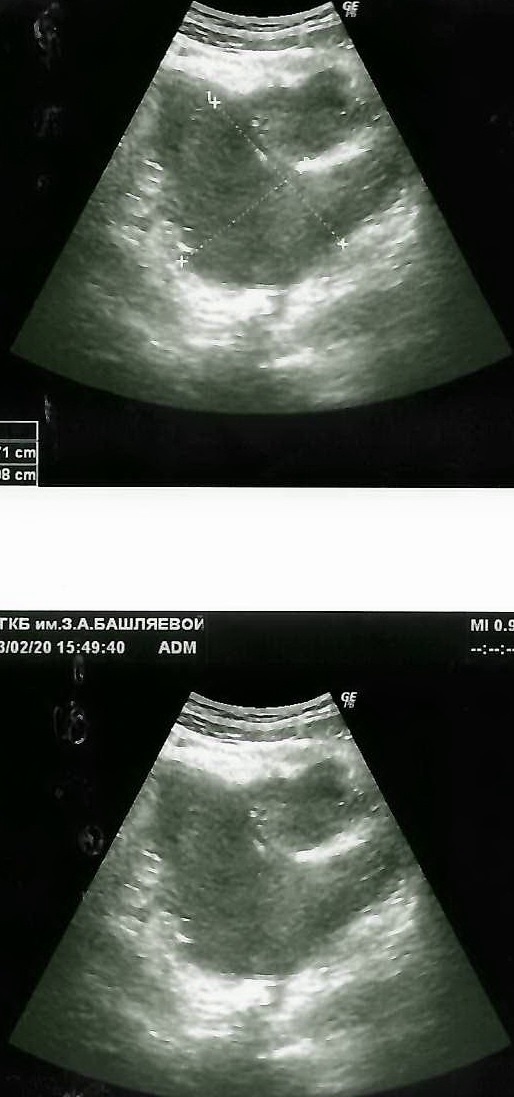

При УЗИ органов брюшной полости в правой подвздошной области определяется тубулярная структура Д 10 мм , с толстыми слоистыми стенками , в просвете определяется эхогенное включение Д 14 мм с эффектом акустической тени (каловый камень), несколько медиальнее определяется инфильтрат неправильной формы размером 51х21х36 мм, содержащий жидкостные включения. Вокруг изменённого аппендикса и инфильтрата определяется сальник. В малом тазу определяется отграниченное жидкостное включение неправильной формы размером 107х48х43мм, без четкой капсулы. Свободная жидкость не определяется. Матка и яичник без патологических изменений. Заключение: Эхо-признаки аппендикулярного инфильтрата, оментита. Формирующийся абсцесс в малом тазу.

Рис 1 – ультразвуковая картина аппендикулярного инфильтрата, оментита

Рис 2- узи картина аппендикулярного инфильтрата с положительной динамикой. Уменьшение размеров инфильтрата на фоне проводимой терапии

Рис 3 – узи картина перед выпиской девочки домой. Выраженная положительная динамика на фоне проводимого лечения